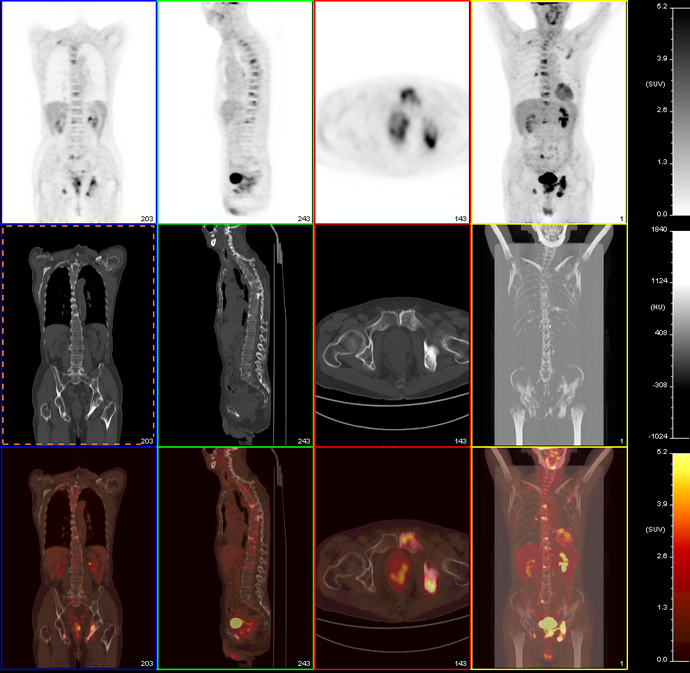

前列腺癌

患者,男性,83岁

夜尿次数多伴骨骼疼痛(下肢

2011.5.24 B超前列腺增生,质地不均匀

血PSA 大于100 TPSA 大于100,尿隐血(++)

PET/CT示:

前列腺FDG代谢不均匀性异常增高,累及直肠前壁,全身骨骼多发成骨性改变伴FDG代谢异常增高,双肺多发结节FDG代谢轻度异常增高,结合病史,考虑前列腺Ca及其转移所致